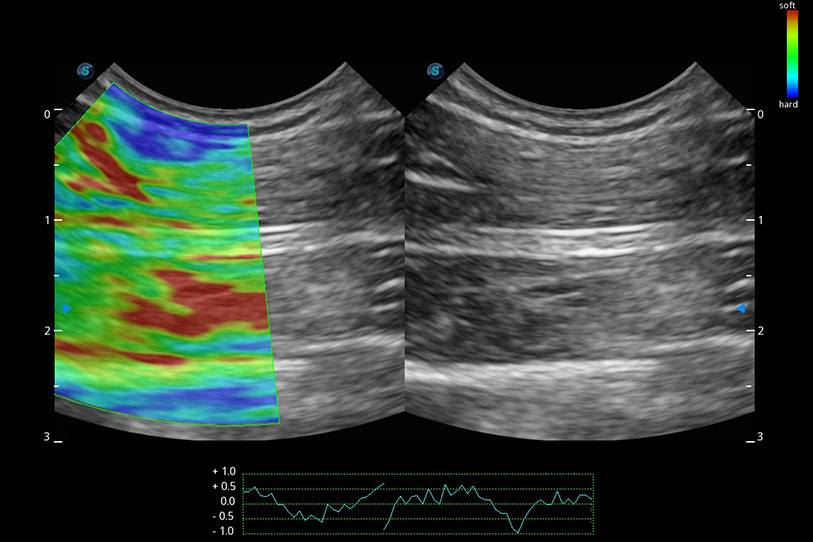

操作簡(jiǎn)便,無(wú)需高頻度外力作用即可真實(shí)反映組織的形變,快速評(píng)估腫瘤良惡性。